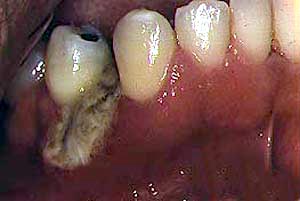

Periodontitis ulceronecrotizante

Secuestro óseo

La periodontitis ulceronecrotizante  se manifiesta en menos del 5% de los casos con pérdida de hueso y tejido blando en los pacientes VIH con recuento de CD4 inferior a 200 y puede progresar a estomatitis ulceronecrotizante

Se encuentran microorganismos usuales de la boca  y organismos ocasionalmente atípicos como  pseudomonas, se han aislado bacilos entéricos y bacterias que no pertenecen a la flora oral..